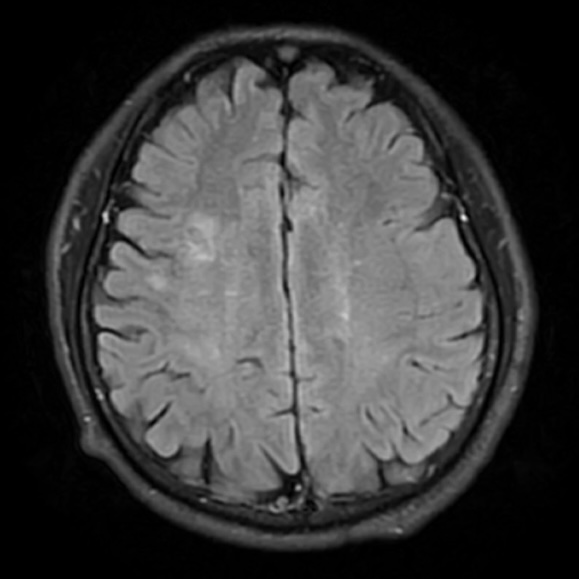

DSA提示患者右侧大脑中动脉狭窄率约95%;PWI提示右额颞顶叶低灌注。

动脉长鞘怎么置入一技之“长”丨经桡及经股困难入路应用赛诺神畅APEX TRA GC™导引导管建立通路病例合集_https://www.jmylbn.com_新闻资讯_第26张

头颅CT

动脉长鞘怎么置入一技之“长”丨经桡及经股困难入路应用赛诺神畅APEX TRA GC™导引导管建立通路病例合集_https://www.jmylbn.com_新闻资讯_第27张

头DWI

动脉长鞘怎么置入一技之“长”丨经桡及经股困难入路应用赛诺神畅APEX TRA GC™导引导管建立通路病例合集_https://www.jmylbn.com_新闻资讯_第28张

头MRI

动脉长鞘怎么置入一技之“长”丨经桡及经股困难入路应用赛诺神畅APEX TRA GC™导引导管建立通路病例合集_https://www.jmylbn.com_新闻资讯_第29张

头MRA